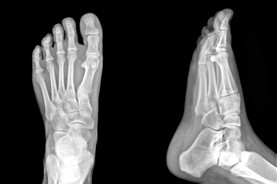

Alberta Foot Doctor & Foot Physical Therapist

The Foot Institute is an association of Alberta Doctors specializing in the medical treatment of the foot and ankle, and is one of the largest groups of foot specialists in Alberta.

The Alberta Foot Institute is dedicated to the medical and surgical treatment of the foot. Our mandate is to provide the best possible medical, surgical and preventative treatment available for our patients. We do this by providing well-trained Doctors who are committed to treat and prevent all types of foot pain, biomechanical disorders, as well as all other problems relating to the feet.

At the Alberta Foot Institute, our Doctors are trained to specifically treat problems associated with your feet or ankles. Below are several of the most common problems that we see on a day to day basis: